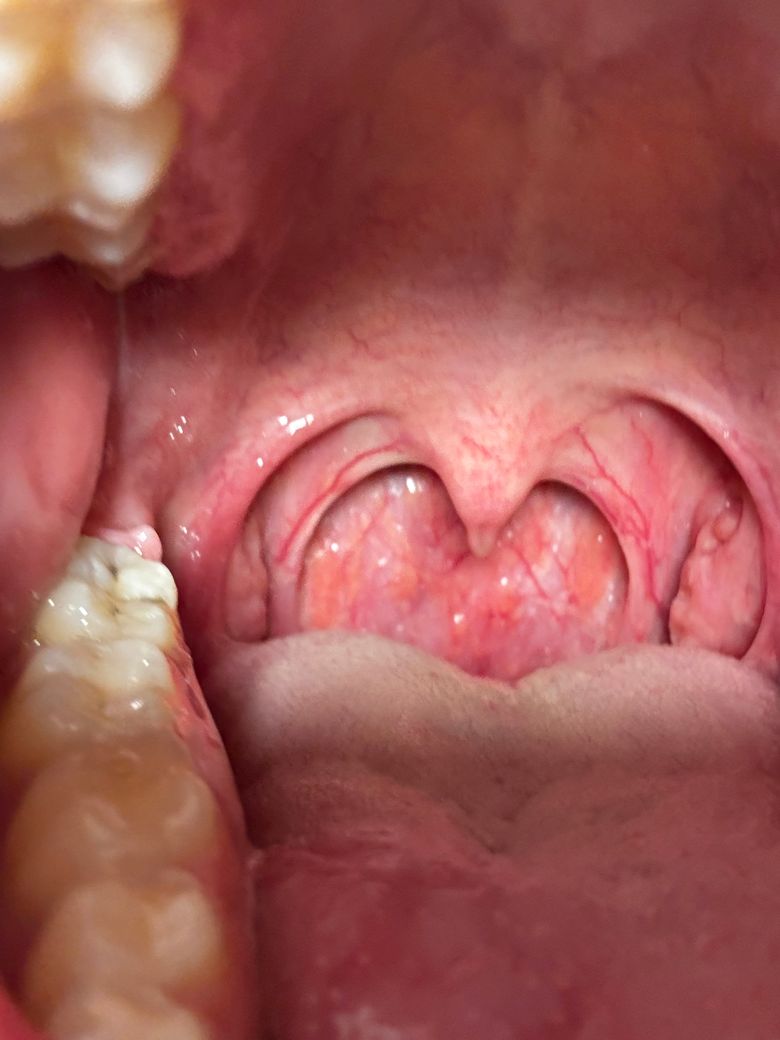

한쪽 편도에 이런게 생겼는데 모양이 이상하네요

최근에 역류성 식도염 증상으로 목이 자주 붇고 좀 뻐근한 경우가 많았었습니다. 목이 불편해 내부 사진을 찍어보니 한쪽 편도의 모양이 조금 비정상적이었습니다. 둥그렇게 파여있는 형태로 뭔가 종기가 볼록하게 나와있는 상태? 인거같은데 뭘까요? 이게 보인지는 한달정도 된거 같고 모양에 큰 변화가 생기진 않는거 같습니다.

사진으로는 정확한 진단 불가능하며 병원 방문하셔서 직접 육안으로 진료 보셔야 합니다

역류성 식도염 외에도 다른 원인이 있을 수 있습니다. 편도가 비정상적으로 둥글게 파인 형태로 보이거나 종기처럼 부풀어 있는 경우는 편도에 염증이나 감염이 있을 수 있으며, 편도 결석이나 낭종이 원인일 수도 있습니다. 종양도 배제 해야 되구요.

정확한 진단을 위해선 이비인후과에 방문해서 진료 및 검사 받아 보셔야 합니다.